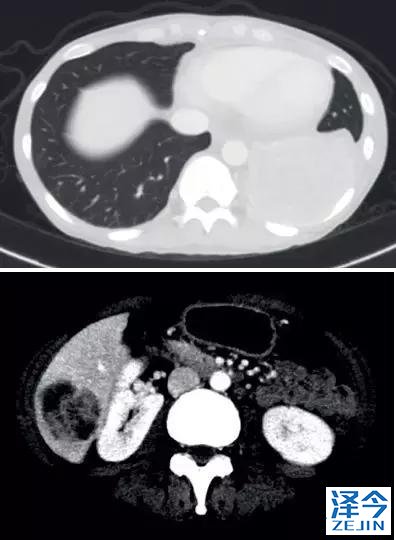

一位77岁的女性患有EPS15-NTRK1 IV期非小细胞肺癌,我们可以看到她的双肺满是病灶,并且出现了肝脏和脑转移,可以说是非常非常晚期了,

肺靶病变达到缓解,我们可以明显的看到前后的图像,病灶明显缩小了,

脑转移病变显示缩小了95%!

初始, 2018年6月 3周期 2018年8月